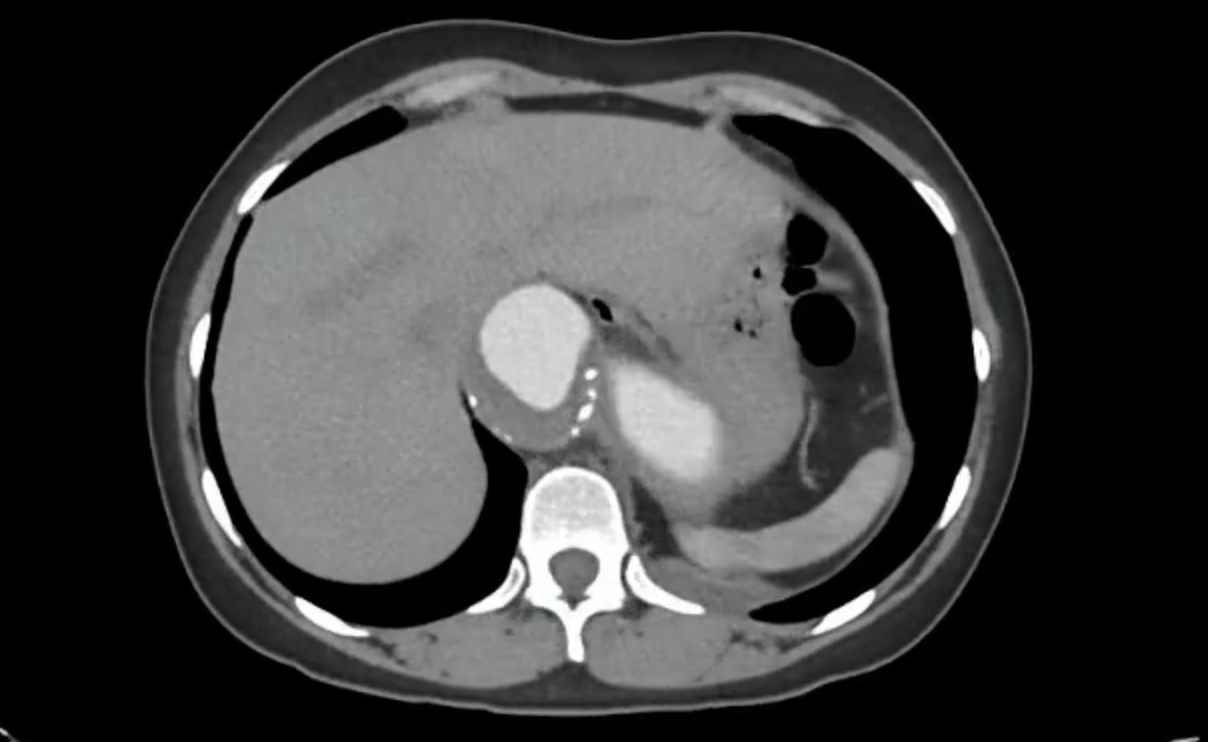

Chest X-ray showed mediastinal widening. CT angiography revealed a fusiform thoracoabdominal aortic aneurysm (89 × 85 mm, 221 mm length) from T6 to L2, with a dissection flap from the coeliac trunk to the infrarenal segment (Stanford B, DeBakey III), plus intramural thrombus and mural calcifications. A 10 mm flap in the proximal coeliac trunk and an intimal tear at the origin of the left subclavian artery (extending 54 mm) were also seen. Additional findings: left pleural effusion and hepatic haemangiomas.

Diagnosis: thoracoabdominal aneurysm with Stanford B, DeBakey IIB dissection. Medical management: IV nitroprusside, esmolol, and analgesia. Due to high rupture risk, endovascular repair was chosen over open surgery. Via right femoral access, two endografts were deployed in the thoracic/abdominal aorta. The left subclavian artery, arising from the false lumen, was not fenestrated. The procedure involved bleeding requiring transfusion, but no further complications.